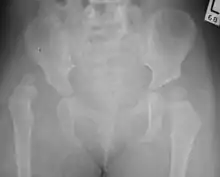

Despite the widespread use of ultrasound, pelvis X-ray is still frequently used to diagnose or monitor hip dysplasia or for assessing other congenital conditions or bone tumors.[45]

The most useful lines and angles that can be drawn in the pediatric pelvis assessing hip dysplasia are as follows:[45] Different measurements are used in adults.[45]